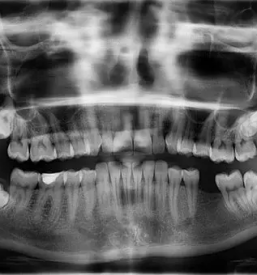

Pri nas smo specializirani za različne storitve na področju zobozdravstva. V naši zobozdravstveni ambulanti

Kljub bogatim izkušnjam, se nenehno izobražujemo in sledimo novostim tako doma kot v tujini, ki jih nato uspešno vpeljujemo v svoje delo, zato se vedno več pacientov odloča za nas, saj jim je pri nas na voljo dobra samoplačniška zobozdravnica. Na Savinjskem boljše ne boste našli.